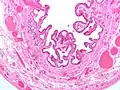

En medicina, la colesterolosis vesicular es la acumulación focal de histiocitos espumosos (macrófagos) cargados de colesterol en la lámina propia de la vesícula biliar.[1]

A veces se llama vesícula biliar de fresa por el aspecto punteado de la superficie de la mucosa en un examen general, similar al que presentan las fresas. La colesterolosis está causada por una acumulación anormal de depósitos de ésteres de colesterol en macrófagos dentro de la lámina propia (células espumosas) y en el epitelio de la mucosa. La vesícula biliar puede estar afectada de forma localizada o de forma difusa. La forma difusa se presenta macroscópicamente como una mucosa roja brillante con motas amarillas (debido a los lípidos), de ahí la comparación con la fresa. No está ligada a la colelitiasis (cálculos vesiculares) ni a la colecistitis (inflamación de la vesícula biliar).[2]

Micrografía de colesterolosis de la vesícula biliar